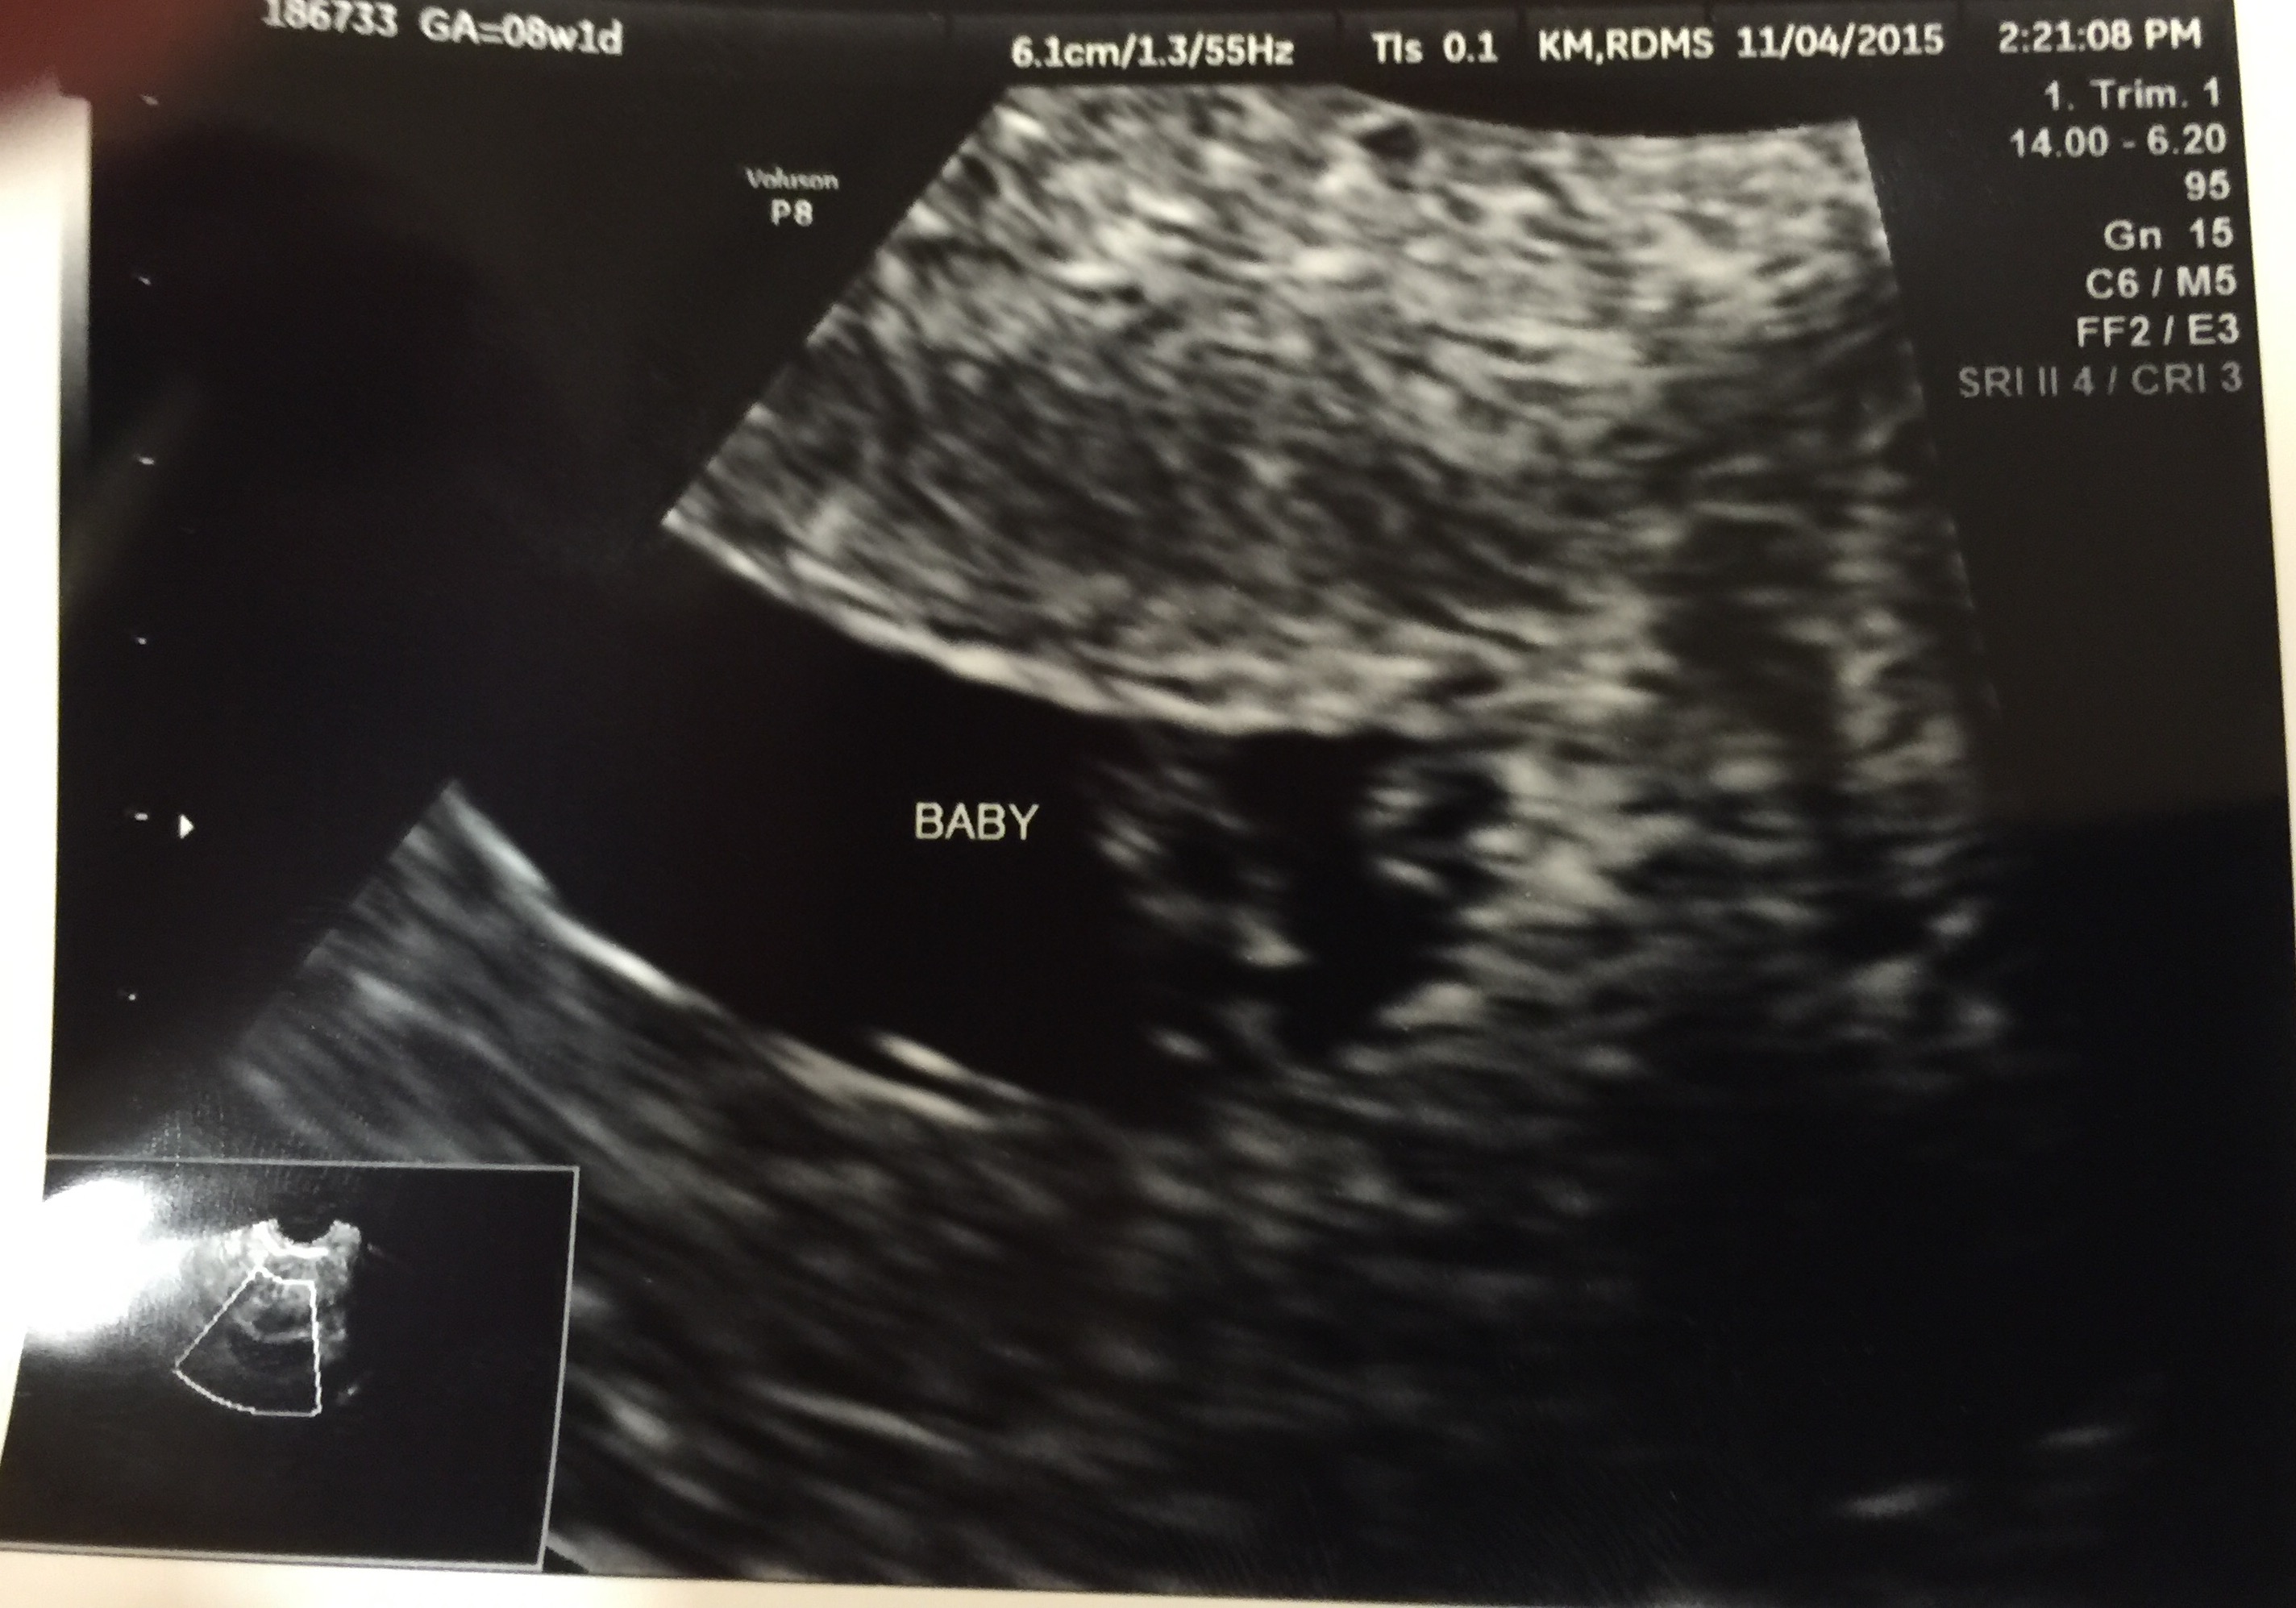

Went in for first official u/s today. 8 weeks 5 days based on LMP. Finally got to see our precious baby and the heartbeat. My OB also pulled out the Doppler and we got to hear it too!! 175 bpm and measuring 9 weeks!! I feel so much better after finally seeing Bean!